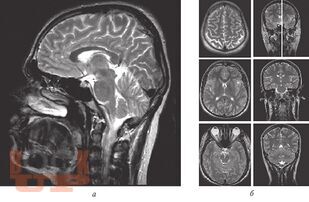

«Атлас нормальной анатомии магнитно-резонансной и компьютерной томографии головного мозга» посвящен актуальной проблеме нейроморфологии и краниологии — прижизненной макроскопической характеристике головного мозга и черепа с применением современных методов визуализации — магнитно-резонансной томографии и компьютерной томографии.

В Атласе представлены более 500 томограмм: магнитно-резонансные томограммы головного мозга, магнитно-резонансные ангиограммы головного мозга, магнитно-резонансные томограммы черепных нервов, компьютерные томограммы головного мозга, компьютерные ангиограммы сосудов головного мозга. Выполнена компьютерная реконструкция костей черепа, дана подробная информация об одном из сложнейших объектов черепа человека — височной кости.

Представленные томограммы могут заинтересовать специалистов в области магнитно-резонансной и компьютерной диагностики не только в качестве эквивалента нормы головного мозга, но и в пределах достаточно широкого диапазона индивидуальной анатомической нормы.